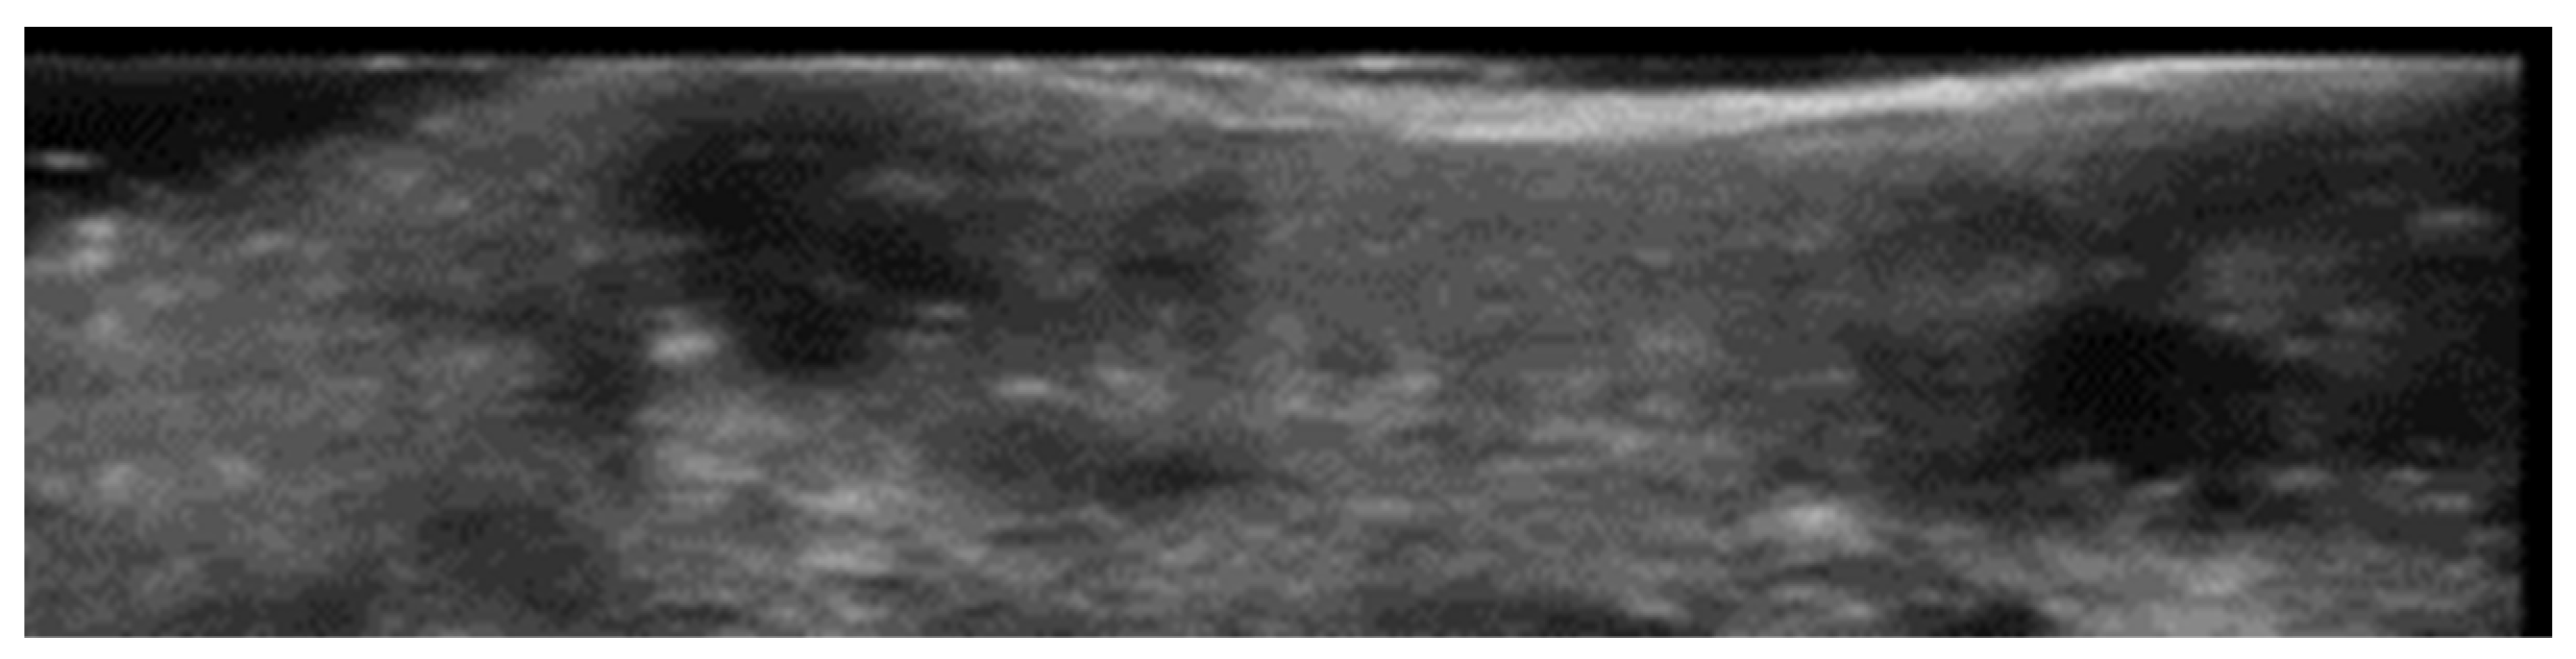

2. Infections

3. Inflammatory Dermatoses